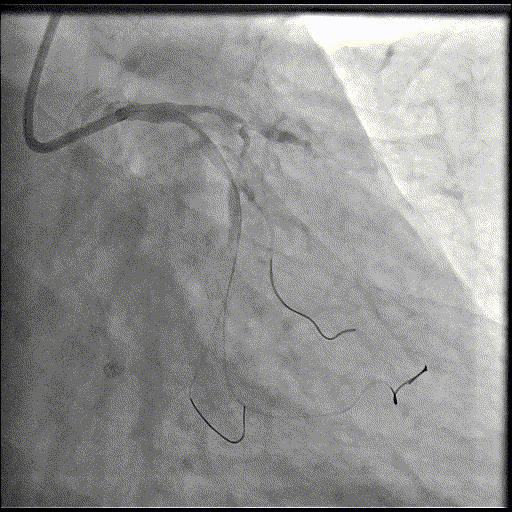

手术经过

导丝到位

当指引导管冠脉开口到位后,选择三根对应导丝分别送入LAD、D1、D2远端。

球囊预扩

选择不同尺寸的预扩球囊逐级预扩张病变,复查造影狭窄减轻不明显。为了解血管真实情况,遂启用IVUS检查。

术前腔内影像学IVUS指导

IVUS提示血管内钙化严重,最小管腔面积不足 4mm²;遂考虑启动IVL治疗。

冲击波球囊治疗

2.5*12mm@4atm 冠脉血管内冲击波导管反复进行8个周期治疗,经IVUS检查提示最小管腔面积增加至4.88mm²;随后选取后扩张球囊对病变行扩张治疗。

支架植入并后扩

于LM-LAD依次植入两枚药物洗脱支架,经非顺应性球囊后扩张支架,复查造影&IVUS提示血管内钙化仍较重,支架贴壁不良,遂再次启动IVL治疗。

再次冲击波球囊治疗

3.0*12mm@4atm 冠脉血管内冲击波导管反复进行5个周期治疗,并选取后扩张球囊对病变行扩张治疗。最终复查造影提示残余狭窄小于10%,未见夹层及血肿,TIMI血流3级。